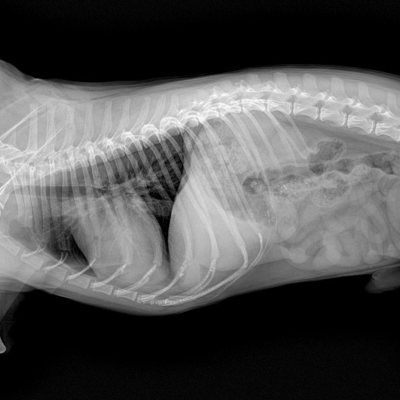

Hayvanınızın iç organları ve kemik yapılarının sağlığını incelemek için röntgen ve diğer görüntüleme yöntemlerini kullanıyoruz. Kan testleri, idrar testleri gibi laboratuvar analizleri yapılır.